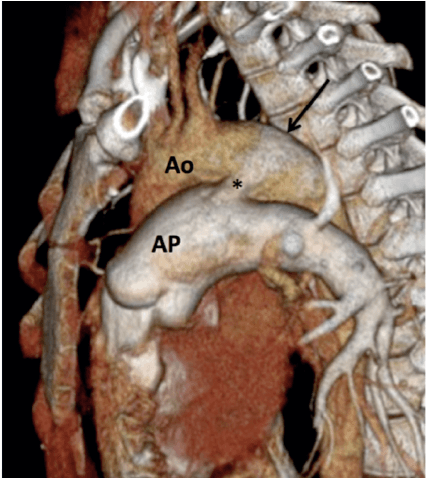

Estrutura vascular que conecta a aorta descendente à artéria pulmonar principal próximo à origem da artéria pulmonar esquerda.